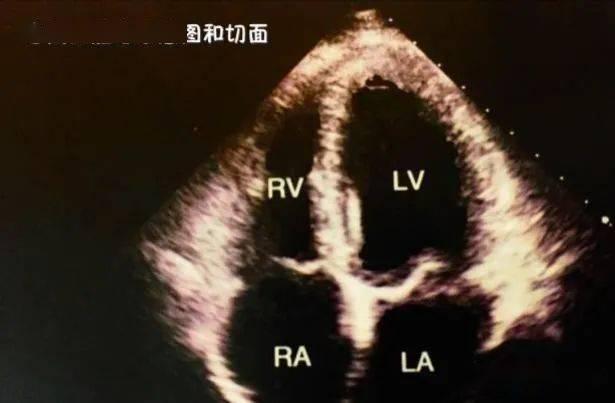

心脏彩超,顾名思义,就是利用超声波技术来观察心脏的结构和功能。它能够清晰地显示心脏的各个部位,包括心房、心室、瓣膜等,还能观察到心脏的跳动和血流情况。对于心脏疾病的诊断和治疗来说,心脏彩超就像是一把“秘密武器”,能够帮助医生们更好地了解患者的病情。

2. 实际操作演示:通过实际操作演示,你可以看到医生是如何操作心脏彩超仪器的,以及如何解读图像。